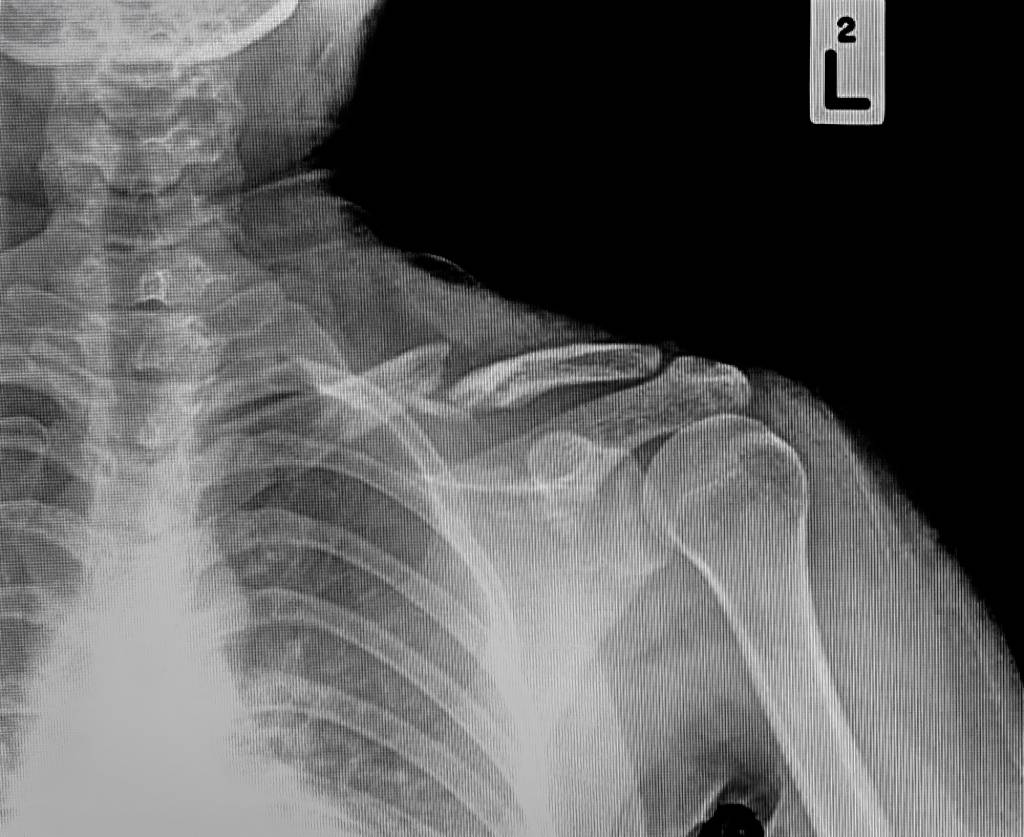

Auf dem Röntgenbild ist der Knochenbruch meist gut zu sehen. Im Zweifelsfall kann eine Computertomographie (CT) angefertigt werden. Eine Kernspintomographie (MRT, Magnetresonanztomographie) kann aufdecken, ob sich weitere Schäden an Gelenken oder Bändern ergeben haben.

Andere Verletzungen von benachbarten Strukturen sind neben der Claviculafraktur (Schlüsselbeinbruch) denkbar. Besonders zu erwähnen ist hier die Ausrenkung im Gelenk zwischen Schlüsselbein und Schulterblatt (Schultereckgelenk im so genannten Acromion). Reißen Gelenkkapsel und Bänder (Schultereckgelenksprengung), so steht das Schlüsselbein ab und kann an einen Knochenbruch denken lassen.